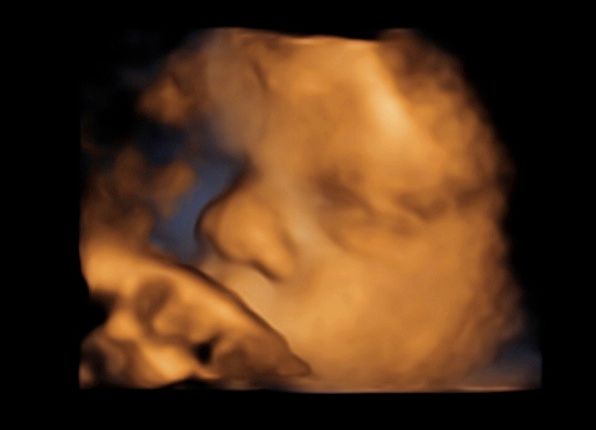

Subito dopo la laurea, il dottor Tommaso Incandela, ha conseguito l'idoneità ospedaliera nella branca di Ostetricia e Ginecologia con il giudizio finale di ottimo. Dall'Aprile 1977 fino al Gennaio 1982, su delibera del consiglio di facoltà, ha svolto la funzione di medico interno della seconda cattedra di Ostetricia e Ginecologia con mansioni didattiche, di assistenza e di cura. Dal Luglio 1981 al mese di Ottobre 1992 ha ricoperto la funzione di assistente di ruolo presso la seconda divisione di Ostetricia e Ginecologia dell'Ospedale Civico e Benfratelli di Palermo. Dal 1 Novembre 1992 fino alla fine di Giugno 1998 è stato dirigente medico del Consultorio familiare di Santa Flavia. Dal Luglio 1998 a tutt'oggi si dedica a tempo pieno all'attività libero professionale occupandosi di ecografia ostetrica e ginecologica con particolare riguardo per la diagnosi prenatale di patologie cromosomiche e malfomative (studio di aneuploidie cromosomiche su DNA fetale prelevato dal sangue materno, amniocentesi precoce, ecocardiografia fetale, ecografia morfologica e cardiotocografia) tutte queste indagini sono inserite nel monitoraggio della gravidanza. Il dottor Tommaso Incandela si occupa altresì di diagnosi precoce e terapia di patologie del tratto genitale inferiore e nel corso degli anni ha acquisito una notevolissima esperienza nell'ambito della terapia conservativa dei fibromi uterini mediante terapia farmacologica e/o inserimento di spirali medicate al progestinico. Da un punto di vista chirurgico il dottor Incandela si occupa di patologie del corpo uterino ivi compresa l'asportazione di fibromi con conservazione dell'utero stesso anche in pazienti meno giovani e con assenza di desiderio di prole. Il dottor Incandela si occupa anche di chirurgia del pavimento pelvico con particolare riguardo per la terapia dell'incontinenza urinaria, dei prolassi uterini e vescicali e delle lacerazioni antiche da parti pregressi.

• Ecocardiografia fetale

• Ecografia morfologica